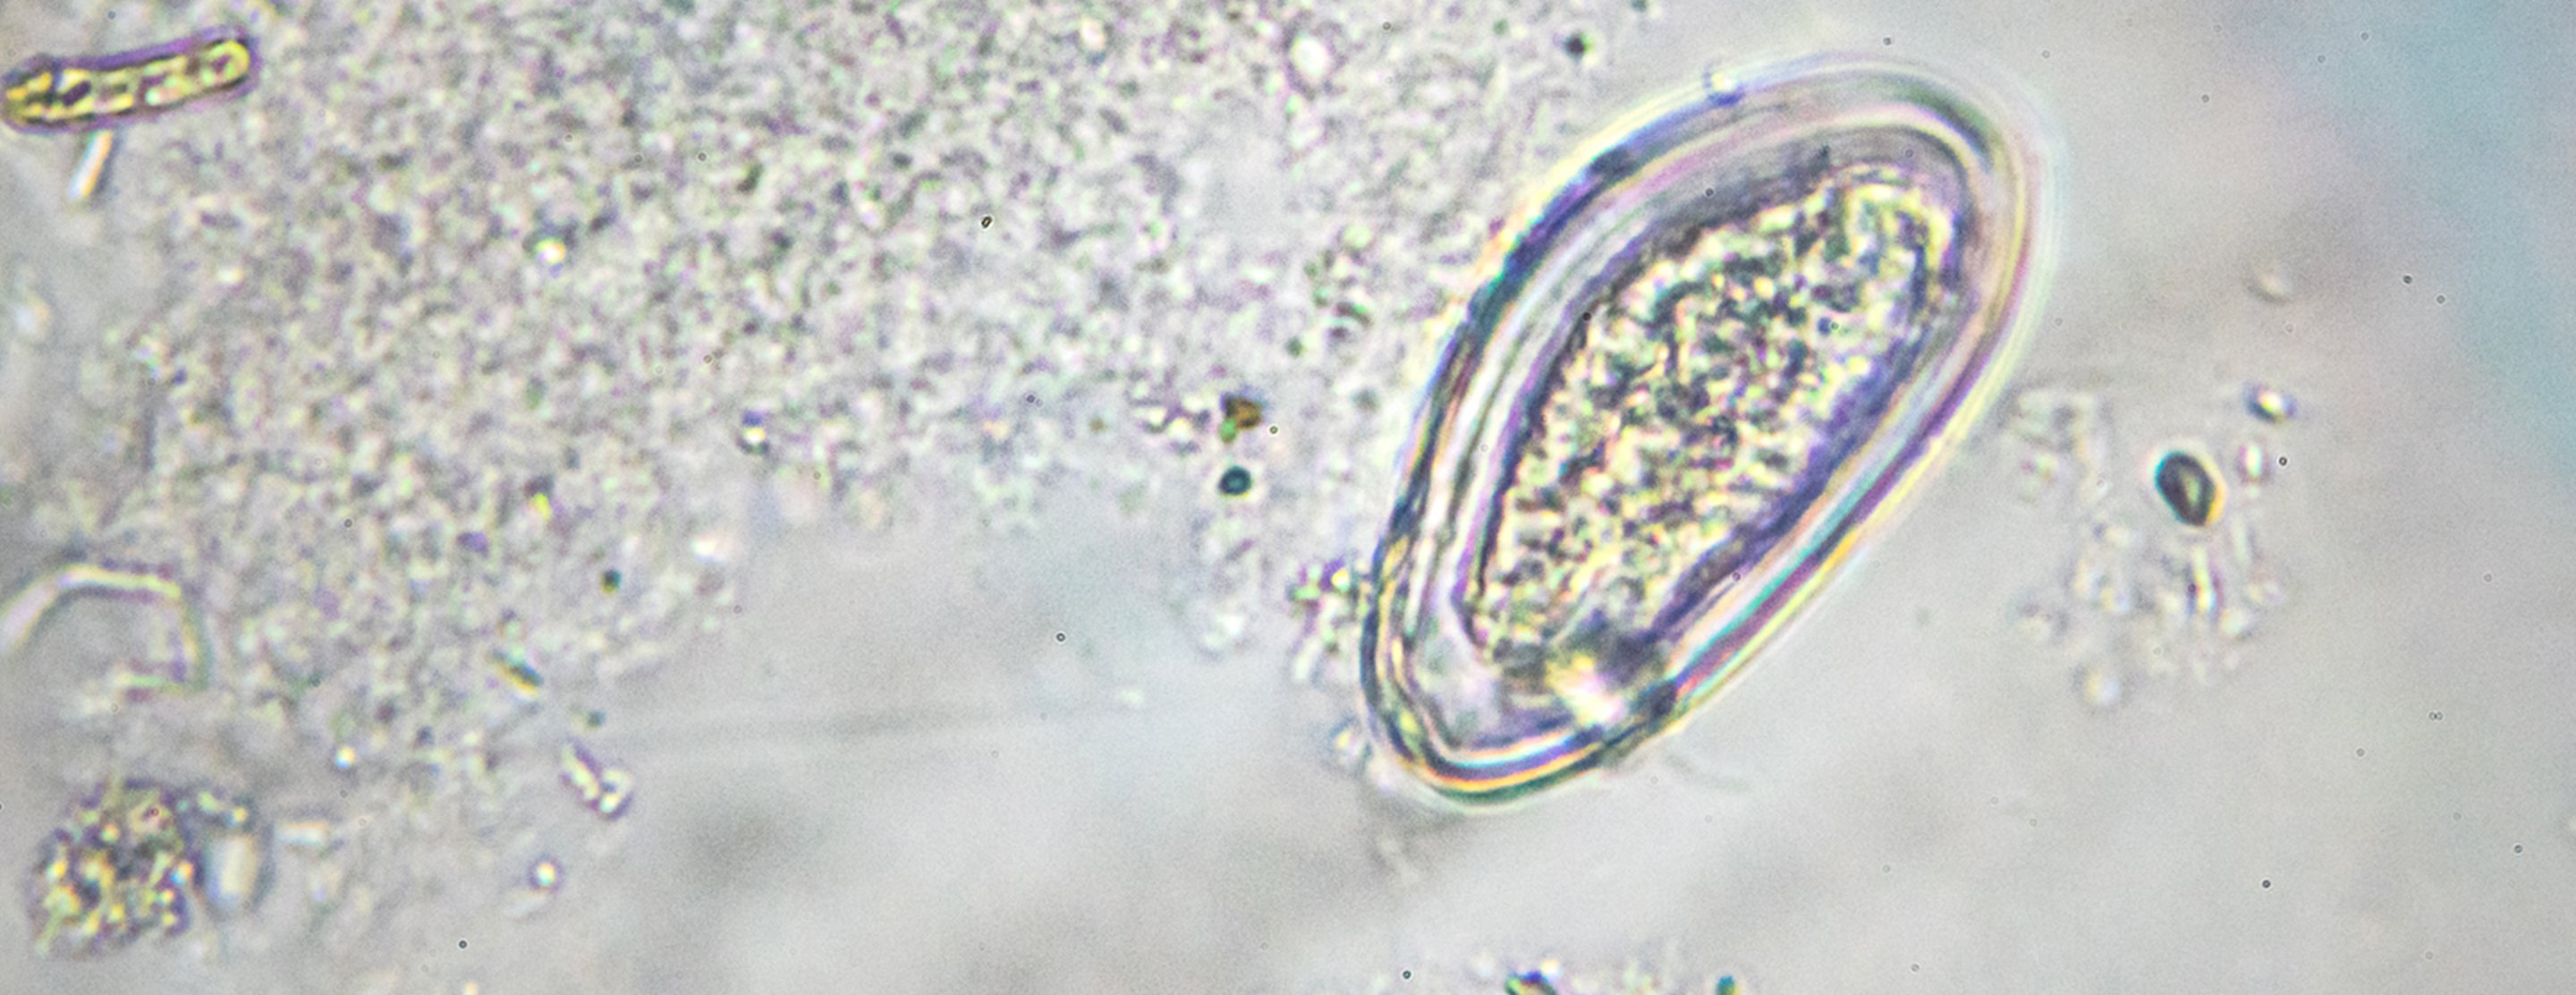

A pinworm test is a method used to identify a

If adult pinworms or eggs are found, the person has a pinworm infection. Usually, all household members need to be treated with medicine. This is because pinworms are easily passed back and forth within a household.